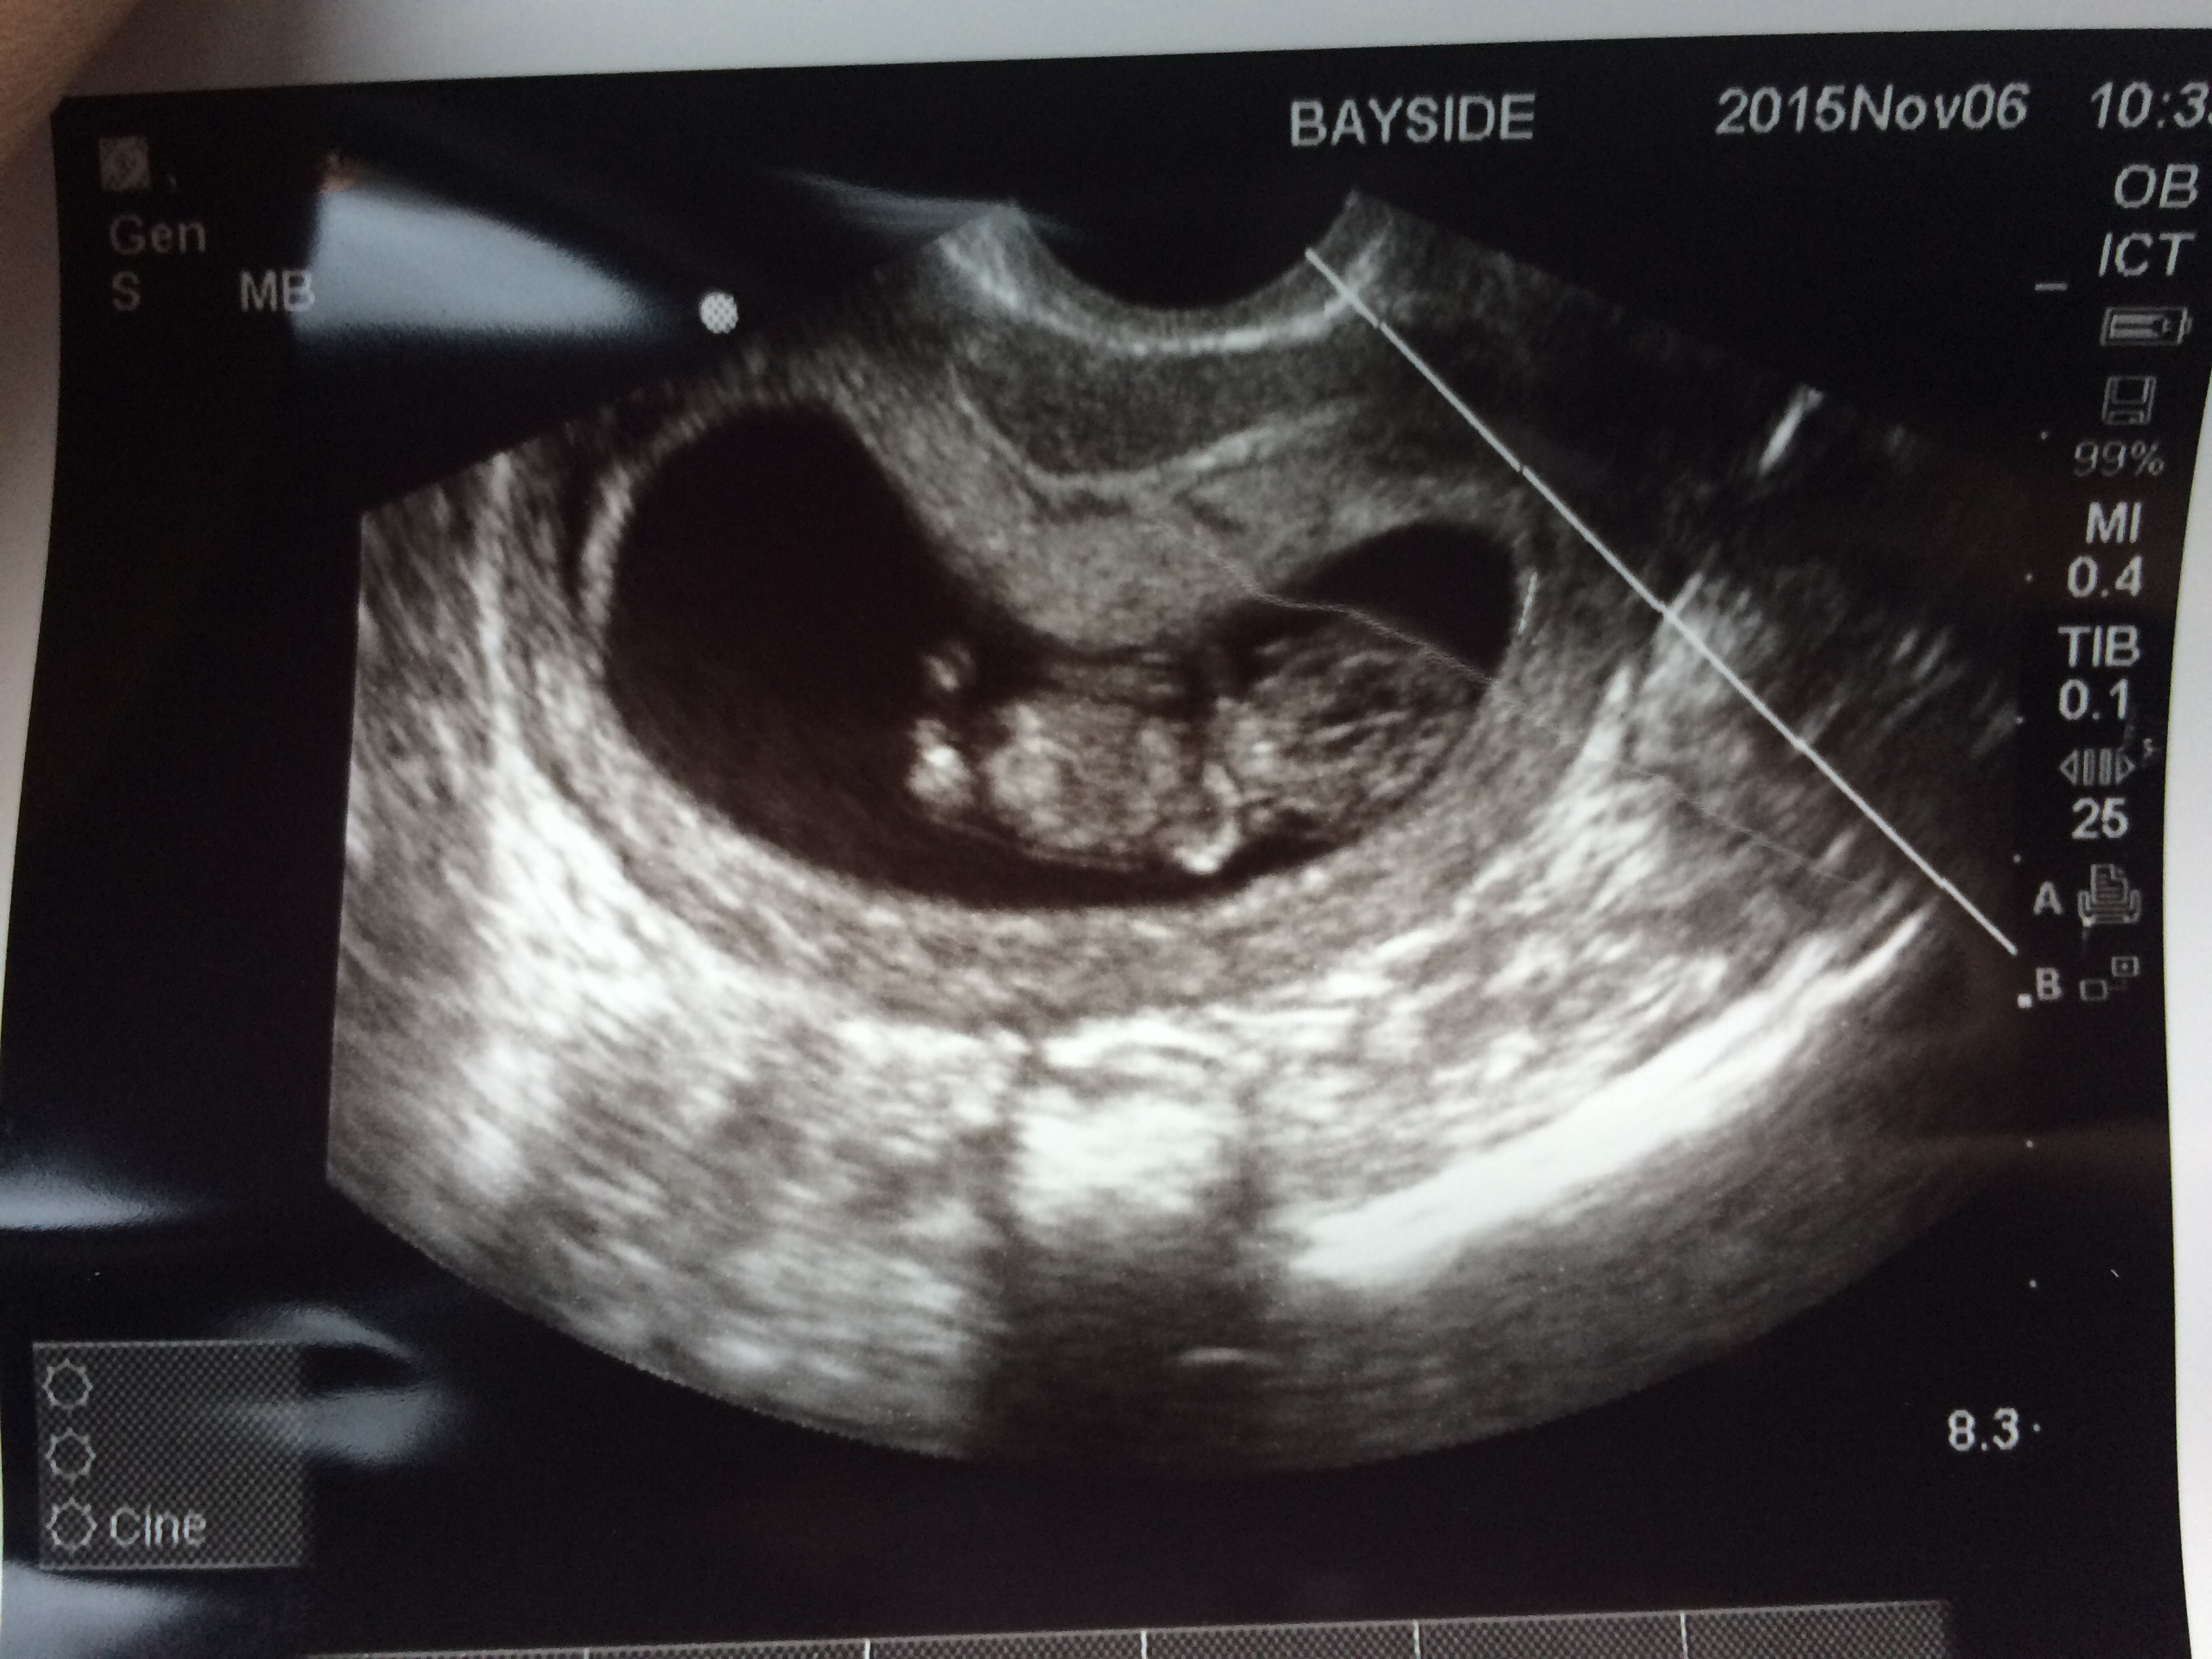

Don't know how I missed this thread before. But I love all of the little peanut pics!!! Our first ultrasound was to confirm pregnancy and we thought based on our last miscarriage and D&C it put us at 5 or 6 weeks but we measured 7 weeks 2 days for that one!

Our first ultrasound was to confirm pregnancy and we thought based on our last miscarriage and D&C it put us at 5 or 6 weeks but we measured 7 weeks 2 days for that one!